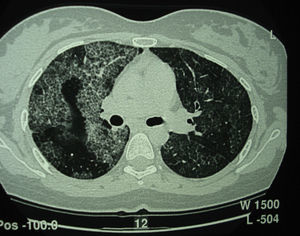

Tomografía computarizada de alta resolución (TACAR) de un pacientes con proteinosis alveolar pulmonar (PAP) que muestra las características clásicas de los septos interlobulillares engrosados contra un fondo de opacidades en vidrio esmerilado, dando la típica una apariencia de crazy paving.

La proteinosis alveolar pulmonar (PAP) es una enfermedad rara que fue descrita por primera vez en el año 19581. Se caracteriza por la acumulación del material lipoproteináceo del surfactante en los espacios alveolares y bronquiolos terminales, lo que puede llegar a producir alteraciones en el intercambio gaseoso2 (fig. 1). Esta acumulación del surfactante es debida a una disminución en su aclaramiento por parte de los macrófagos alveolares, siendo característica la presencia de macrófagos alveolares con inclusiones de material fosfolipoproteico. Su incidencia estimada es de 0,2-0,4 casos por millón de personas/año, con una prevalencia de 3,7-6,2 personas/año3. Hasta el año 2002 se habían descrito en la literatura unos 410 casos4.